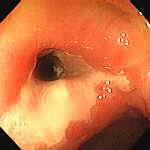

Leziunile precoce sunt granularitatea mucoasei, cu stergerea luciului si hiperemie. Apar ulterior ulceratii mici, superficiale, care cresc progresiv in dimensiuni. In fazele active pot fi acoperite de exudat muco-purulent sau hemoragic. In zonele de confluenta a ulceratiilor apar si denivelari - pseudopolipi inflamatori -zone de regenerare a mucoasei,cu tesut de granulatie, ce nu se malignizeaza.

RCUH - stadializare endoscopica

|

STADIUL 0 (remisiune) |

Mucoasa palida, vase tortuoase (scurte, fara ramificatii de ordinul 2,3) |

STADIUL 1 (activitate usoara) |

Mucoasa granulara, hiperemica, fara luciu, cu vase partial vizibile; poate sangera usor la atingerea cu endoscopul |

STADIUL 2 (activitate moderata) |

Mucoasa hiperemica, edematiata, retea vasculara absenta, uneori mici ulceratii; sangereaza spontan sau la atingerea cu endoscopul |

STADIUL 3 (activitate severa ) |

Mucoasa hiperemica, edematiata, cu ulceratii multiple de dimensiuni variabile (2-4 mm), superficiale, neregulate, care sangereaza difuz la atingerea cu endoscopul, acoperite pe alocuri de exudate mucopurulente si hemoragice |

Stadiul 1 Stadiul 2 Stadiul 3